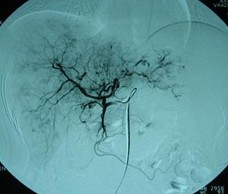

患者情況:肝細(xì)胞性肝癌,術(shù)后復(fù)發(fā),右肝內(nèi)多個(gè)病灶。治療方案:瘤內(nèi)注射今又生1×1012VP/次/周,共8周,同時(shí)聯(lián)合肝動(dòng)脈化療栓塞(TACE),1次/月,共2次。下圖示:左側(cè)上下兩圖為治療前,CT示血管豐富;右側(cè)上下兩圖為治療一個(gè)療程后,碘油均勻沉積,腫瘤血供減少。